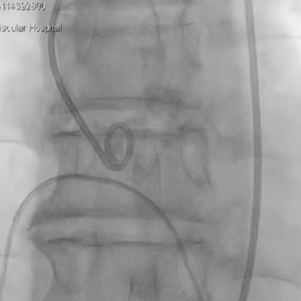

从三叶瓣重度钙化到二叶瓣畸形的根部解剖,从单纯主动脉瓣反流到入路极端迂曲挑战的案例。TaurusOne凭借其优异的柔顺性,支撑力强及内外层双侧裙边的特点,都能从容应对复杂的临床患者解剖结构。从患者的临床选择到术后的长久获益,从手术入路的种类到术中操作的注意事项,从围术期卒中的循证医学到术后的抗凝抗栓用药规范,在线专家共同交流彼此中心的围术期TAVR经验和分享现阶段经导管主动脉瓣置换的诊疗策略。针对当前TAVR领域多个热点学术问题进行了热烈的讨论,现场可谓精彩纷呈、高潮迭起。专家们纷纷借此契机相互交流探讨,分享各自的单中心经验,力求进一步提升TAVR手术的安全性和有效性,为主动脉瓣相关疾病的患者带来长远综合获益。